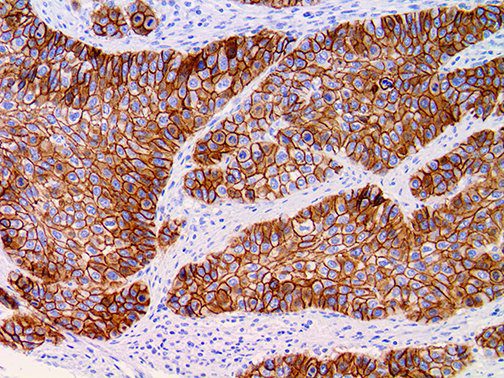

The first cytokines released are interleukin 1β (IL-1β) and tumor necrosis factor-α (TNF-α), which attract a variety of circulating white blood cells (WBCs) to the infection site, including neutrophils, monocytes, macrophages, and natural killer (NK) cells. This response, along with the antipathogenic chemicals released by these cells (i.e., complement), comprise the innate immune response. These cells directly attack the invading pathogen and also release additional cytokines, chief among them interleukin-1 and 6 (IL-6). IL-6 is essential for invoking the adaptive immune response, which calls T-cells, B-cells, and T helper (Th) cells to the infection site. IL-6 also stimulates further recruitment, proliferation and activation of macrophages.

It is the ICU physician who is most likely to witness one of the deadliest manifestations of the abnormal immunological response, the cytokine storm syndrome (CSS). This response is also referred to by some as the cytokine release syndrome (CRS). CSS is characterized by continuous activation and expansion of macrophage and lymphocyte populations, which secrete large amounts of cytokines, causing the cytokine storm. This massive cytokine release is akin to hemophagocytic lymphohistiocytosis (HLH) disease, a syndrome characterized by initial unchecked and persistent activation of cytotoxic T lymphocytes and NK cells.